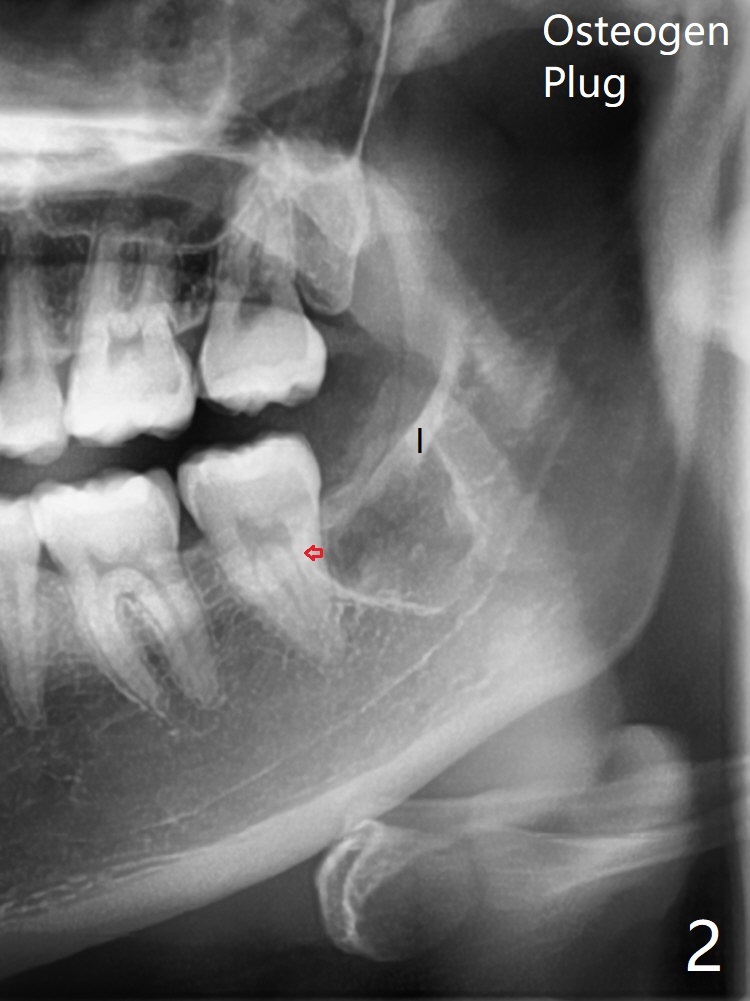

A 20-year-old woman requests extraction of the lower left 3rd molar (Fig.1). In fact the tooth being buccal to the 2nd molar is ignored preop (Fig.1,2 red arrow). The vertical incision is placed too distal with subsequent elevation of the mesial flap. From now on every panoramic X-ray should be viewed with magnification before surgery! After extraction, one piece of Osteogen Plug is placed; the anterior end of the Internal Oblique Ridge (Fig.2 I) is located in the posterior of the socket. As the socket heals, the anterior end of the ridge is expected to advance.